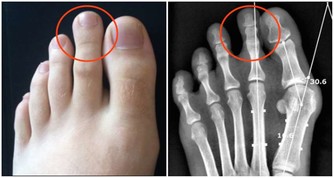

骶髂關節位於薦骨和髂骨之間,使骨盆保持穩定。當骶髂關節出現問題時,也可能導致胯骨疼痛的發生。骶髂關節功能失調主要與姿勢不良、勞損、產後骨盆鬆弛等因素有關。

長期維持不良的姿勢是導致骶髂關節問題的常見原因。例如久坐或長時間駕駛時,腰薦部容易處於前凸的姿勢,薦髂關節承受較大的壓力,而久站或高跟鞋也增加薦髂關節的負擔。這些都可能導致骶髂關節不穩定、錯位,造成骨盆周圍肌肉收縮,進而感到胯部疼痛。

重複的扭轉、擠壓、搬重物等勞損也可導致骶髂關節受損。這類動作帶給薦髂關節周圍韌帶和肌肉反覆疼痛,長期下來,關節功能逐漸失調。患者常在翻身、改變姿勢時感到胯部和薦骨疼痛。

此外,女性在生育後,骨盆結構和韌帶會有所鬆弛。這導致骶髂關節更容易發生位移和不穩定。

根據報告,約有45%的產婦會出現骶髂關節不穩定的情況,其中2/3伴隨明顯的骨盆或胯骨疼痛。

當骶髂關節發生細微挫傷或錯位時,周圍肌肉會出現保護性痙攣,這也可能導致胯骨局部疼痛。雖然痙攣是身體對骶髂關節損傷的一種恢復反應,但也可能加劇胯骨的不適感。嚴重時,也可能壓迫到骶髂關節附近的薦神經,產生放射痛。

若骶髂關節受損導致的胯骨疼痛持續存在,不僅影響生活,也容易誘發腰薦部肌肉間的紊亂。這進一步加重骶髂關節的負擔,形成惡性循環。

因此,出現這類疼痛時,應儘早透過調整姿勢、適度運動等方式治療,以防止問題持續惡化。婦女產後也應注意骶髂關節的運動和恢復。只有使骶髂關節恢復正常的結構與功能,才能從根本緩解相關的胯骨疼痛問題。